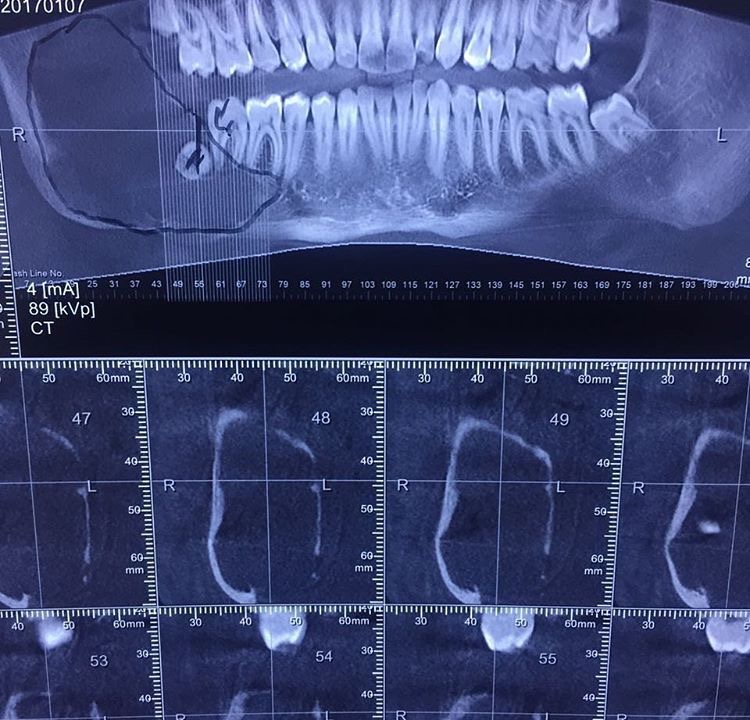

Diş Estetiği ve İmplant (Bölüm 1)

Tansel Hamza